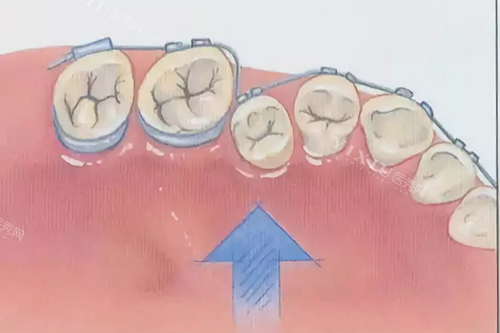

同时,麦绚口腔配备了一系列新型的口腔诊疗设备,如智能化口腔 CT 机、3D 口腔扫描仪、智能种植导板系统等。这些设备能够精细获取患者口腔数据,为医生的诊断和治疗提供科学依据,大大提高了诊疗的明确性和效率。无论是复杂的种植牙手术,还是精细的牙齿矫正治疗,都能在这里得到正规、有效的解决。